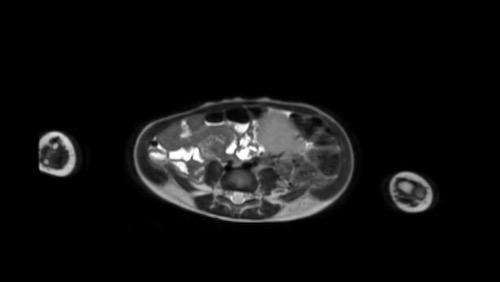

Mức độ lan rộng của khối u được đánh giá rõ ràng trên chuỗi xung TSE T2 weighted 3D theo mặt phẳng axial.

The left kidney is compressed and displaced caudally.

Có di căn hạch bạch huyết cạnh động mạch chủ (mũi tên vàng nhỏ).

Nguyên ủy của thân tạng và động mạch mạc treo tràng trên bị khối u bao quanh (đầu mũi tên).

Tĩnh mạch chủ dưới bị đẩy ra phía trước (mũi tên xanh).

Xẹp phổi hai bên ở vùng lưng thường được thấy trên MRI, vì việc kiểm tra được thực hiện dưới gây mê.